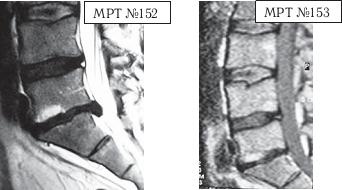

И ещё один пример устранения секвестрированной грыжи межпозвонкового диска.

На МРТ № 152 наблюдается секвестрированная грыжа межпозвонкового диска в сегменте LV-SI.

На МРТ № 153 наблюдается состояние поясничного отдела позвоночника после одного курса лечения методом вертеброревитологии.